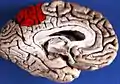

![]() Medial surface of left cerebral hemisphere. (Precuneus visible at top left.) (Anterior to the right.) | |

Medial surface of left cerebral hemisphere. (Precuneus visible at top left.)